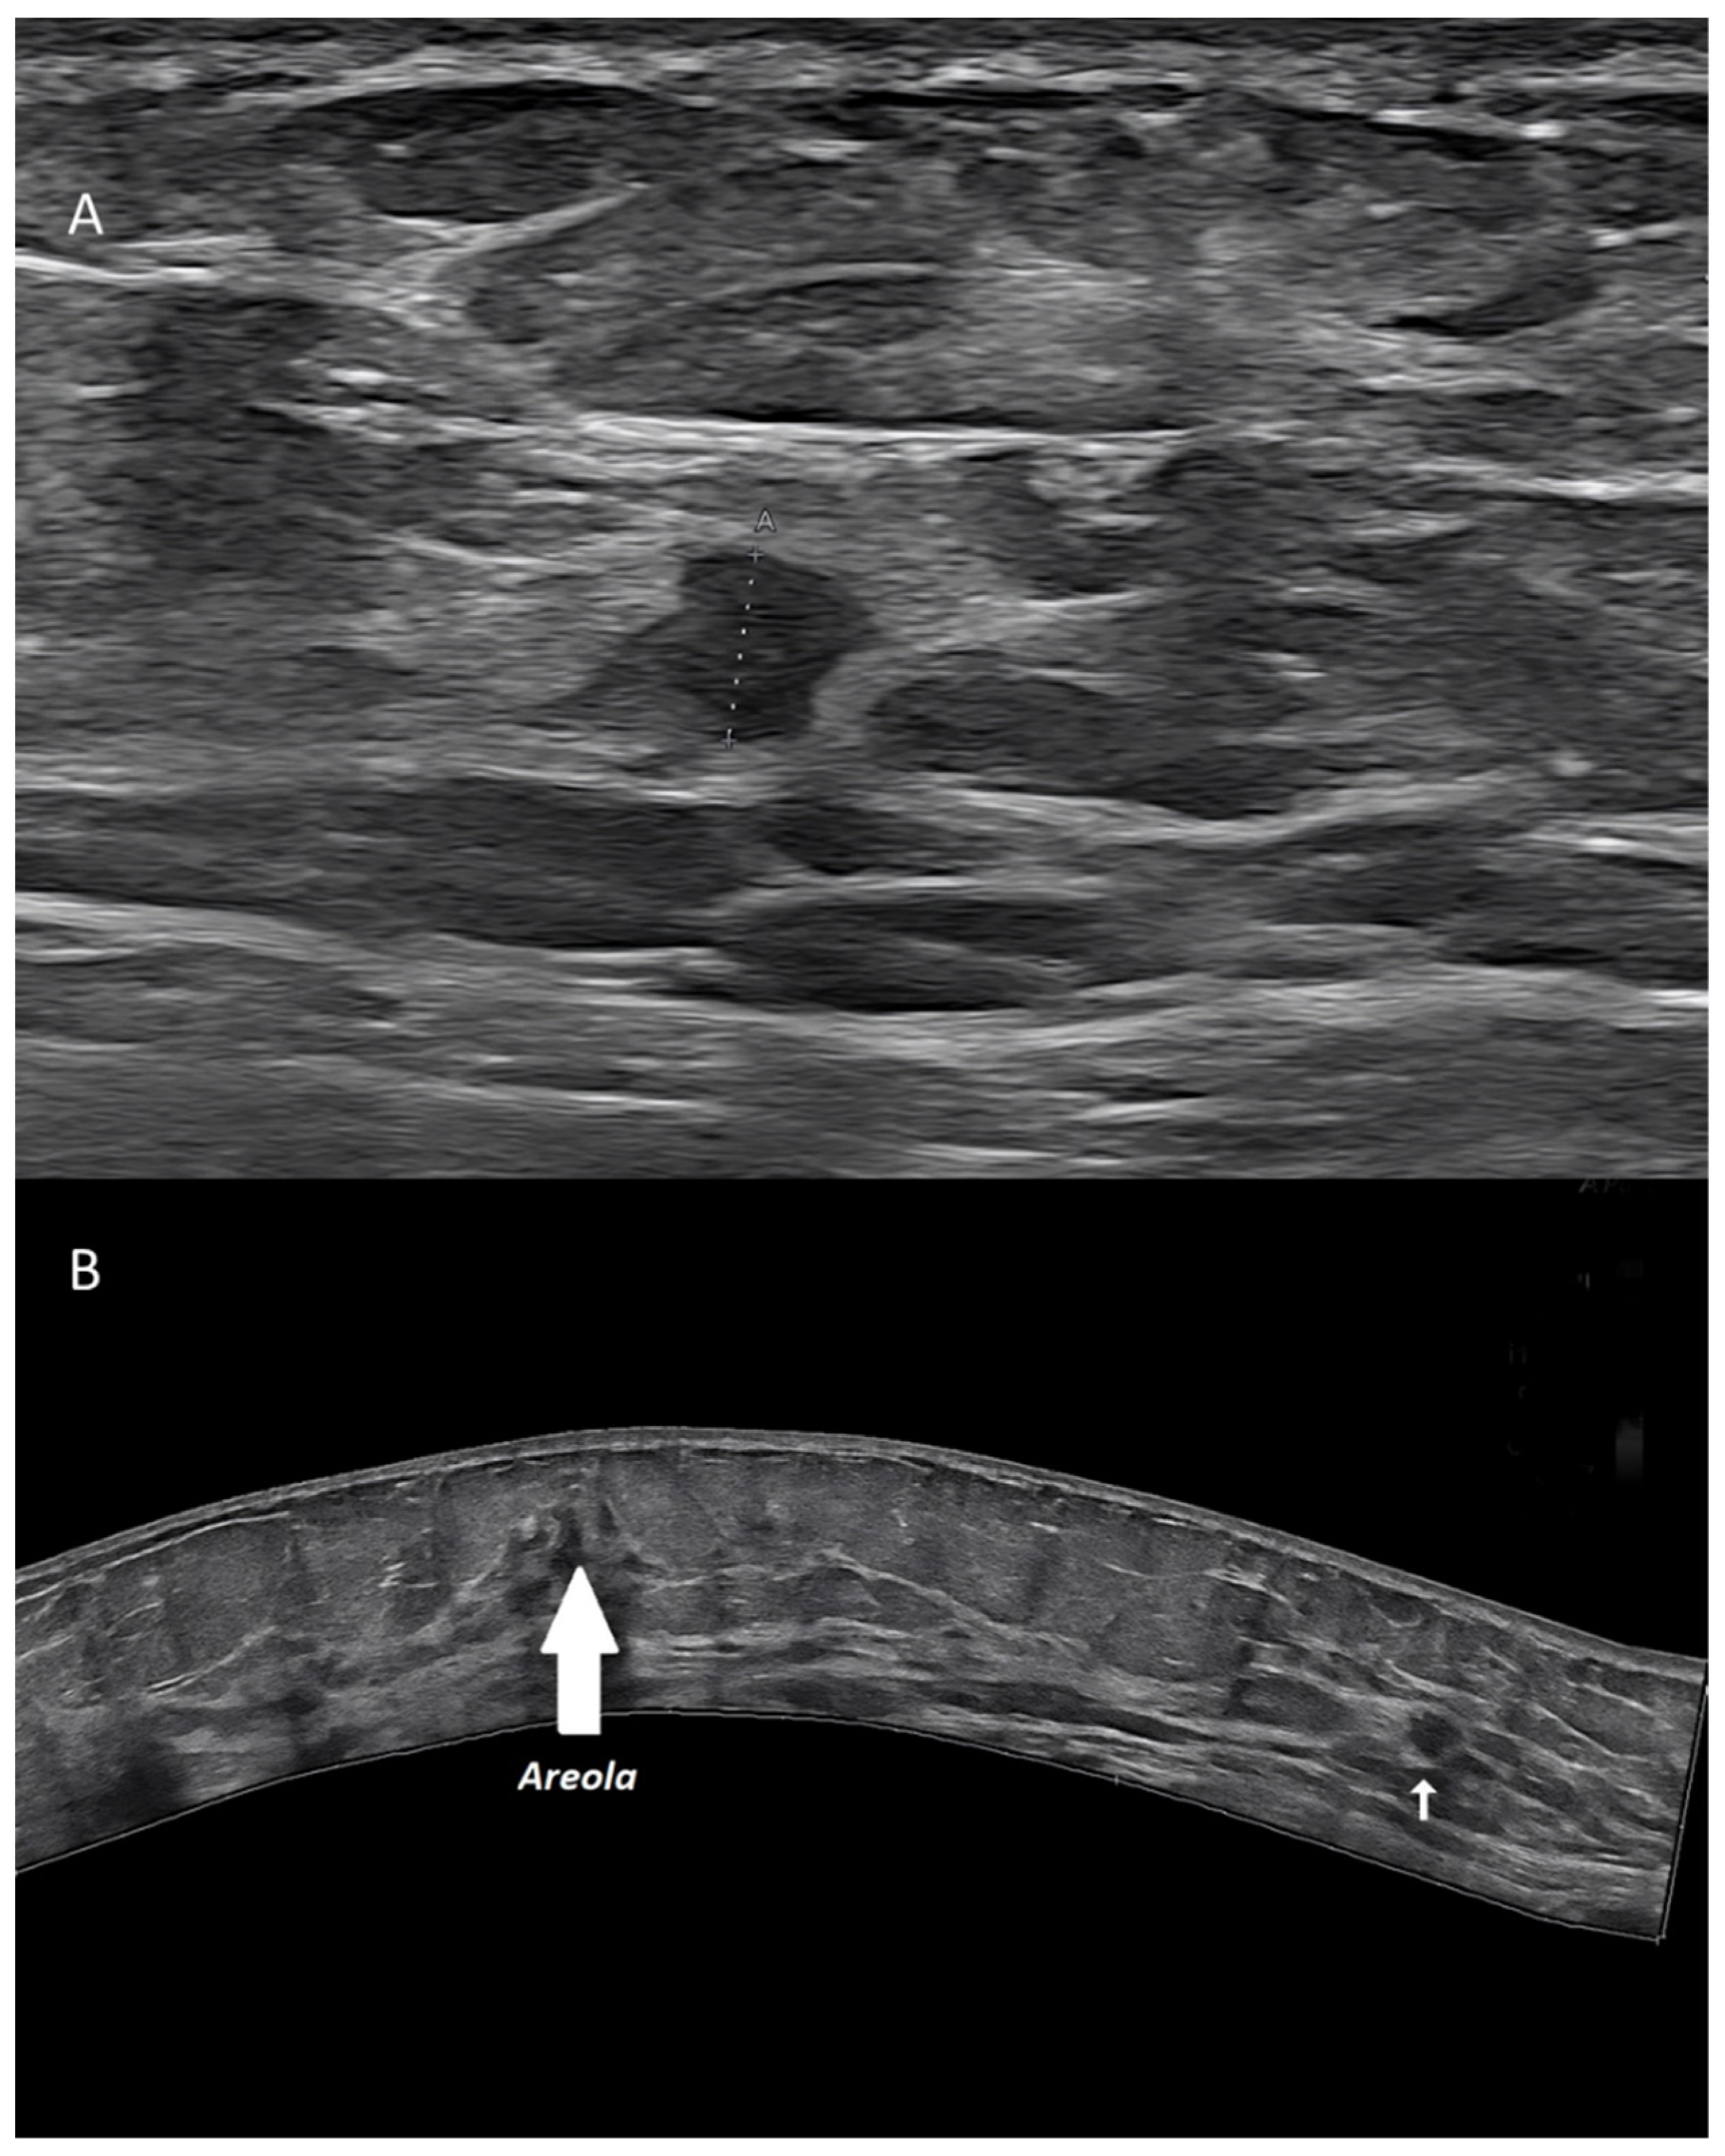

Figure 3. Invasive ductal carcinoma of the breast. (A) US scan showing a 4-mm nodule (calipers). (B) Extended FOV scan displaying the nodule (arrow) within the whole breast.

US has a limited field of view (FOV), not allowing to display, in a single scan, a breast area larger than the probe footprint itself [11]. Extended FOV systems allow to partially encompass this limitation. Starting from a real-time translational movement of the probe over the skin, the software can continuously compare the position and create a large 2D image, without any loss in terms of spatial resolution.

Extended FOV scans allow to display and measure large breast lesions. Additionally, it becomes possible to show the spatial relationship and the distance between a lesion and some anatomic landmarks, such as the nipple, or between multiple lesions, as for multifocal/multicentric cancer [13] (Figure 3). Images of the whole implant can be obtained, being particularly useful for plastic surgeons.